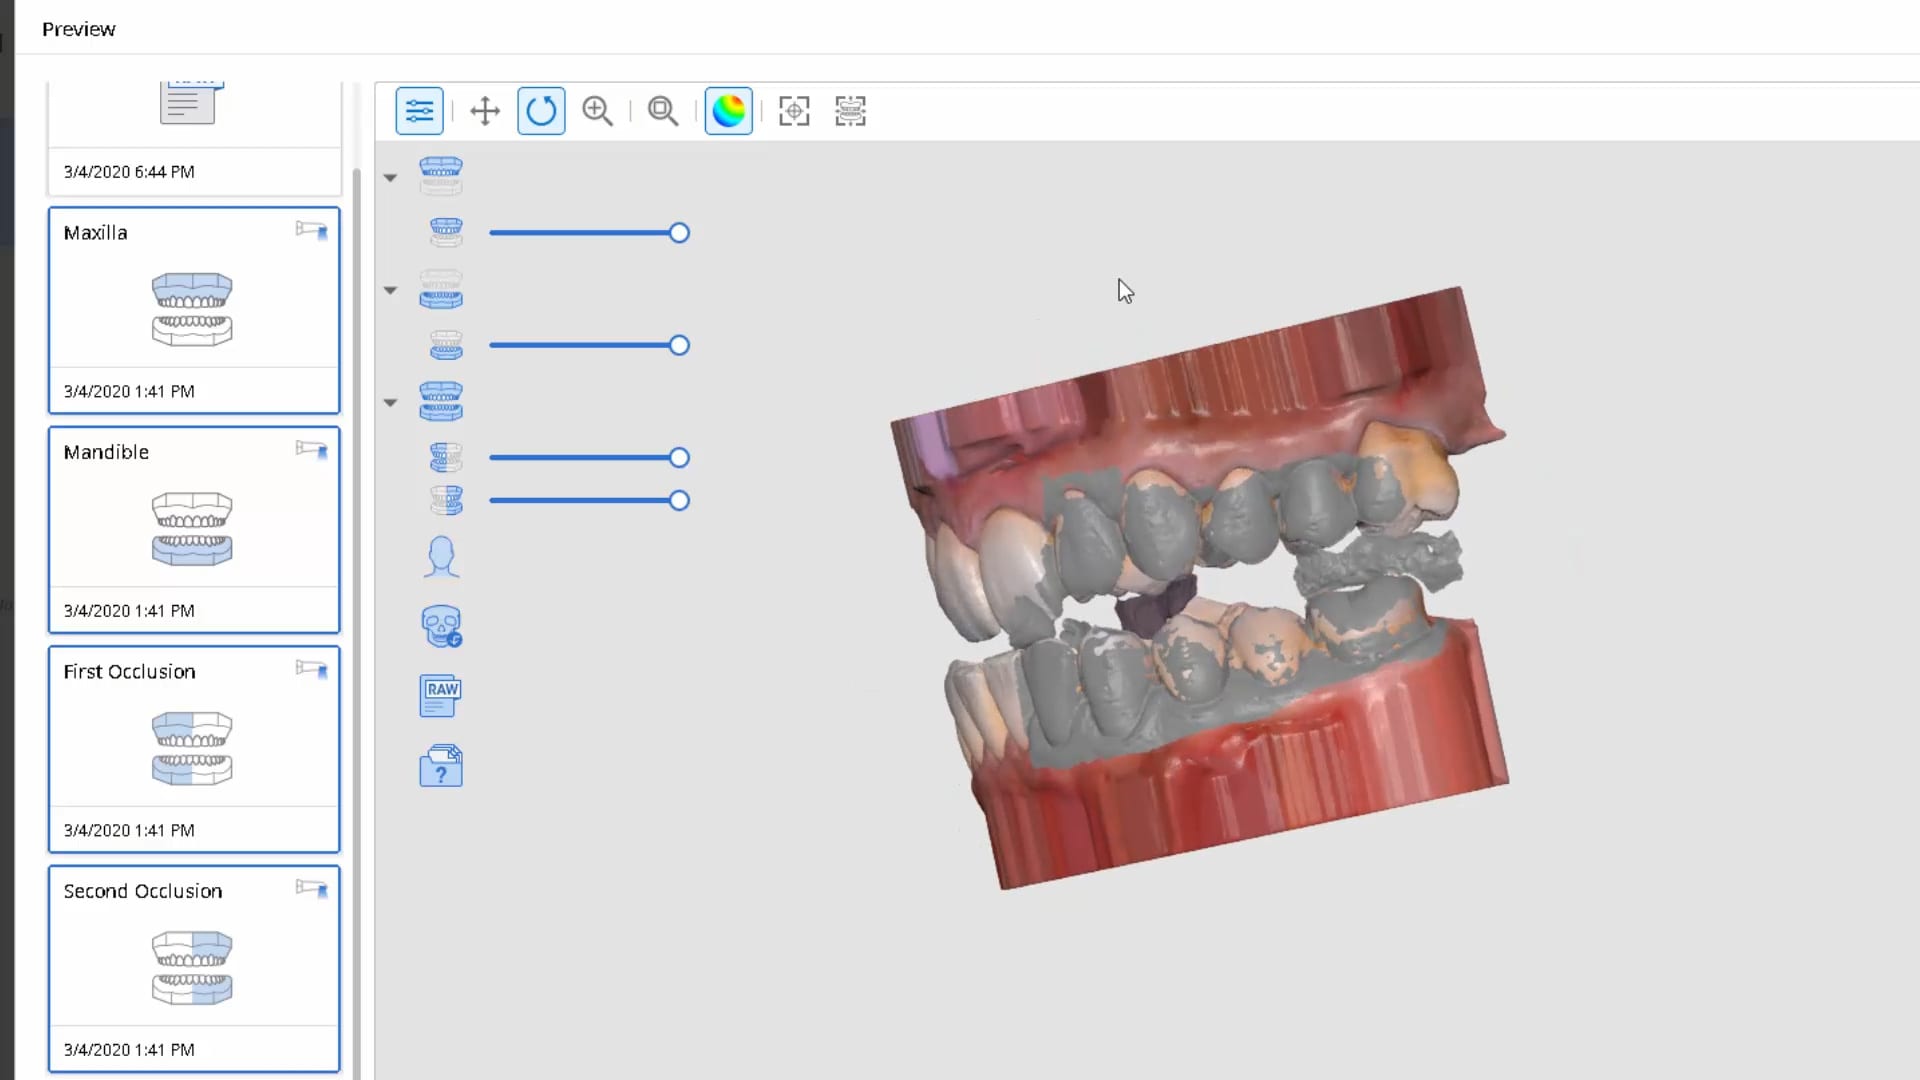

March 9, 2020Most manufacturers recommend that you start your imaging at the second molar area, which is the least practical area to start with. The tongue and the lip and saliva are […]